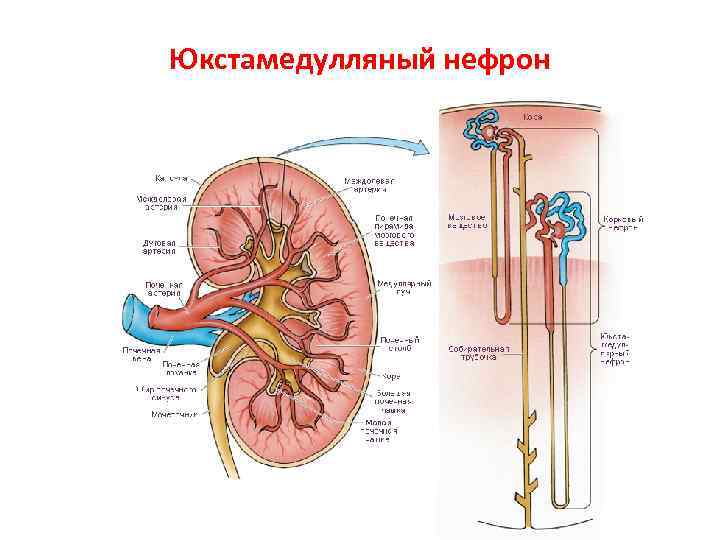

Юкстамедулляный нефрон

Юкстамедулляный нефрон

Особенности строения юкстамедуллярных нефронов по сравнению с корковыми нефронами: 1. Приносящие артериолы по диаметру равны выносящим 2. Петли Генле более длинные и спускаются почти до верхушки сосочков 2. Выносящие артериолы не распадаются на околоканальцевую капиллярную сеть, а спускаются в мозговое вещество, где каждая из них распадается на несколько прямых параллельных сосудов. Достигнув верхушки пирамиды, они возвращаются обратно в корковое вещество и впадают в междольковые или дуговые вены.

Особенности строения юкстамедуллярных нефронов по сравнению с корковыми нефронами: 1. Приносящие артериолы по диаметру равны выносящим 2. Петли Генле более длинные и спускаются почти до верхушки сосочков 2. Выносящие артериолы не распадаются на околоканальцевую капиллярную сеть, а спускаются в мозговое вещество, где каждая из них распадается на несколько прямых параллельных сосудов. Достигнув верхушки пирамиды, они возвращаются обратно в корковое вещество и впадают в междольковые или дуговые вены.